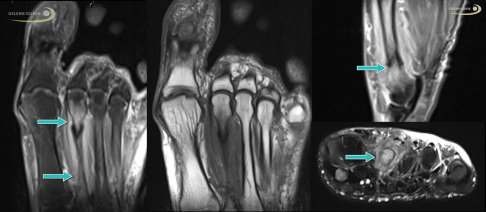

MRT zur frühen Erkennung einer Stressfraktur

Die Magnetresonanztomographie (MRT) ermöglicht bereits eine frühe und aussagekräftige Diagnose. Mit dem Schichtbild lassen sich Knochenhautreaktionen und Knochenmarködeme darstellen, die einen frühen Hinweis auf eine mögliche Stressfraktur liefern.

Beim Verdacht auf einen navikulären Ermüdungsbruch wird die Bildgebung eingeleitet. Meist führt man zunächst eine belastete Röntgenaufnahme einschließlich Schrägaufnahme durch. Allerdings sind Röntgenbilder oft erst einmal negativ. Hilfreicher ist die digitale Volumentomographie (DVT). Mit ihr lassen sich Frakturlinien besser erkennen und auch Fissuren, also winzige Risse im Knochen, gut darstellen. Eine kernspintomographische Untersuchung (MRT) ist ebenfalls möglich, bei deutlichem klinischem Verdacht aber nicht unbedingt erforderlich. Die MRT kann jedoch helfen, wichtige Differenzialdiagnosen auszuschließen.

Zur Stellung der exakten Diagnose einer Stressfraktur werden häufig mehrere bildgebende Verfahren wie die digitale Volumentomographie (DVT), die Computertomographie (CT) oder die Magnetresonanztomographie (MRT) miteinander kombiniert.

Die vielversprechendste Möglichkeit zur Erkennung von Stressfrakturen im Bereich der Fußgelenke ist die digitale Volumentomographie (DVT). Dieses radiologische Verfahren macht Knochen- und Gelenkveränderungen durch die Erstellung von Schnittbildern bereits im Anfangsstadium der Erkrankung sichtbar. Häufig entstehen Stressfrakturen am Fuß im Bereich des Innenknöchels mit Beteiligung des Sprunggelenks, wo sie durch die DVT schon früh nach dem Auftreten erster Symptome erkannt werden können. Im Gegensatz zum MRT-Bild sind für die Diagnosestellung mittels DVT allerdings immer Veränderungen der Knochenstruktur notwendig, um Stressfrakturen sicher zu ermitteln. Das bildgebende Verfahren wird neben der Diagnostik auch zur Operationsplanung eingesetzt.